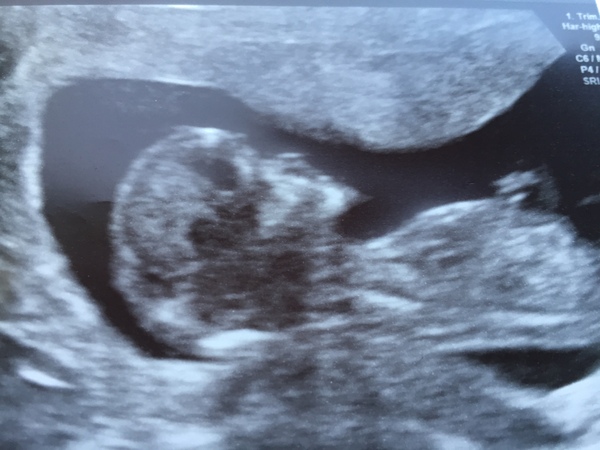

MrsPotatoHead80 · 05/12/2016 06:41

Had my NHS scan yesterday & back to where I thought I should be at 12+4 Smile

Baby was being a tad uncooperative so lots of jiggling about required to try & get it in the right place.